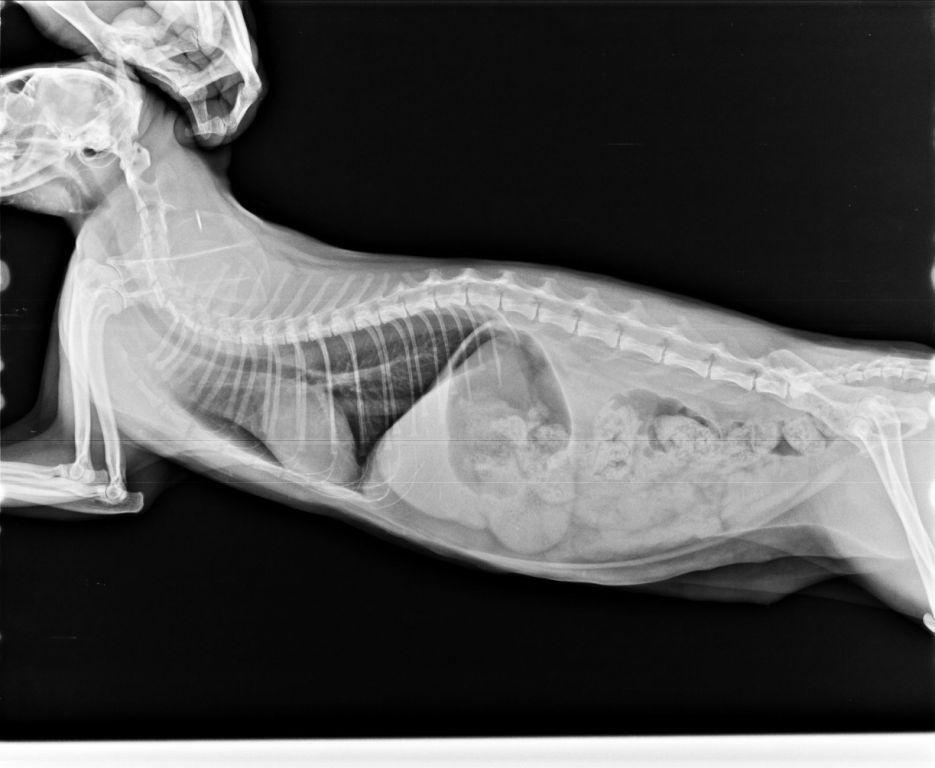

白親親於6/17 日班照護員發現眼瞼翻出且口水狂流不止

因此緊急帶往醫院就診,由於狀況突然因此醫院也做了細菌培養

找出白親親嚴重的呼吸道感染是否有其他病毒因素

白親親於住院期間由於嚴重的口水不止以及鼻塞導致張口呼吸

不吃不喝因此院方替白親親裝設食道胃管

治療後逐漸穩定而出院